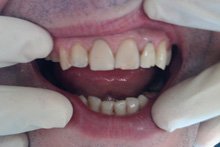

Сохранить зубы и пародонт помогает правильная гигиена полости рта дома и в кресле стоматолога, а также своевременное протезирование и имплантация, которые замещают удаленные зубы и равномерно распределяют жевательную нагрузку, не позволяя костной ткани атрофироваться.